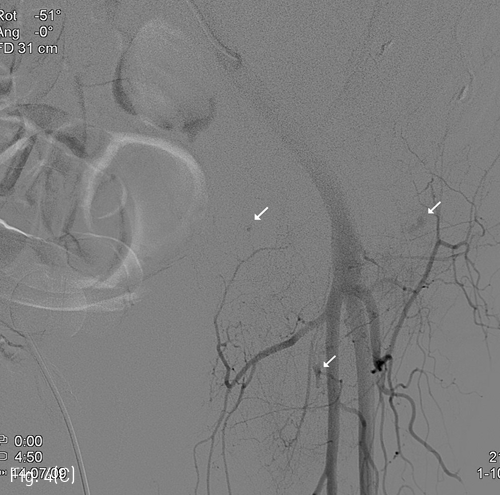

Fig 4C

(C) Additional extravasation foci were noted at branches of the left proximal deep femoral and femoral circumflex arteries, which were treated with glue embolization.